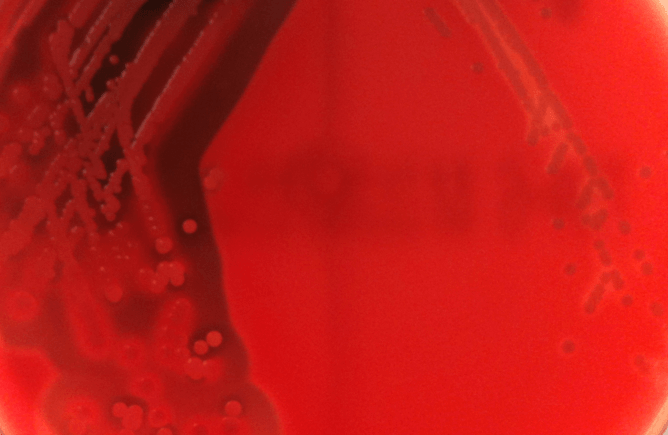

为了试着去了解细菌感染严重程度的差异,我们把注意力放在这些细菌分泌毒素的能力上:毒素就是能够物理性破坏人体细胞的蛋白质。在下图中可以看到细菌产生的毒素对血细胞的影响。图片左侧生长着剧毒细菌,可以看到血细胞破碎的溶血环,而图片右侧生长着无毒素的细菌,血细胞完整无损。

含有马血的琼脂平板上生长着剧毒和低毒性的MASA。(图片来源:作者提供)